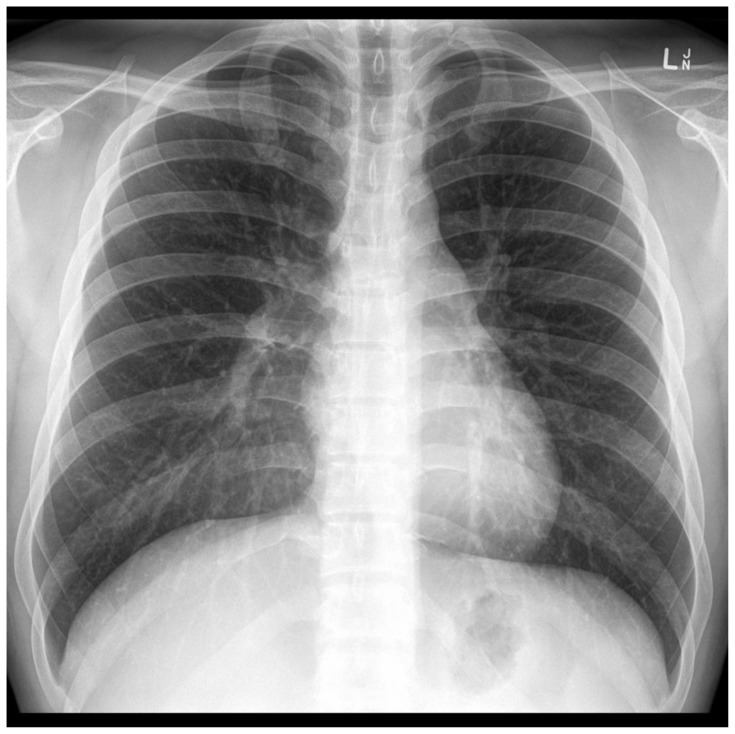

Abstract Image